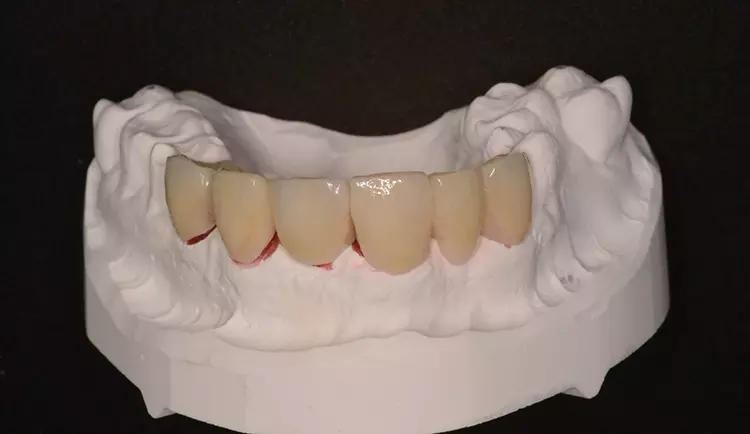

Neuversorgung Oberkieferfront auf Altimplantat 21

Die 49-jährige Patientin beklagte die ungleiche Höhe der Schneidekanten an den Kronen 11 und 21. In diesem Zusammenhang wurde das Gesamterscheinungsbild analysiert und entschieden, die Zähne 13-23 zu überkronen und dabei die Altkronen an 11 und an dem Implantat 21 zu erneuern. Die verschachtelt stehenden Zähne im Unterkiefer sollen im Nachgang per Aligner-Therapie ausgerichtet werden.

Dabei wurde die beabsichtigte Situation im Vorab per Wax-up simuliert. Beim Entfernen der Altkrone 21 wurde ersichtlich, dass ein Titanabutment eingesetzt wurde, an dem sich Konkremente und Zementreste befanden, die zu einer marginalen Mukositis am Implantat führten.